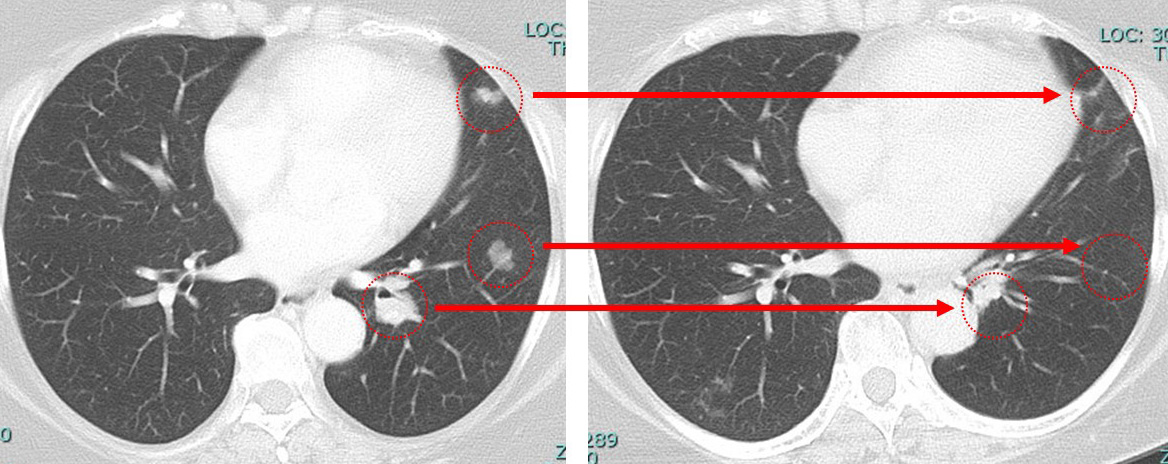

1.肺病変を「転移なのか?の確定診断目的+(局所療法としての)切除目的+(転移ならば)サブタイプを確認する目的」で(胸腔鏡下に)切除⇒その後全身療法

2.まずは全身療法(やはりfirst line はsacituzumab govitecanとなるでしょう)

⇒(肺病変が)消失しないのであれば「ここで」肺の手術

上記1,2どちらにせよ、まずは「画像上完全緩解cCR」 それをどの位維持できるか? この維持が10年を超えた時、それは根治の可能性を秘めてきます。

その後、肺病巣は摘出しサブタイプ待ちの状態であると「質問3」があり、それに対し(もしも原発巣同様のトリプルネガティブであれば)

肺 かなり効いている

肺転移は(分子標的薬だけで)コントロールされている。

①「多発肺転移」は画像上かなり小さくなっているのに「胸の腫瘍は小さくならない」

anthracyclin終了時の時点でのCTでcCR